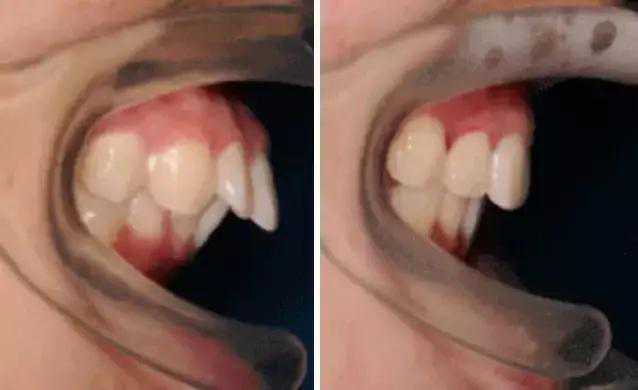

牙性(dentaltype)由牙或牙槽垂直向发育异常引起,也就是仅有牙齿向前突,牙齿长轴角度倾斜过大,但是上下颌骨的形态、大小及在矢状方向上的相互关系基本正常,面部畸形不明显,你的上唇和鼻子周围是不鼓的。

这类嘴凸患者非常适合正畸,通过拔牙+打钉的方式,往往整个牙就能获得翻天覆地的变化。

矫正前vs矫正后